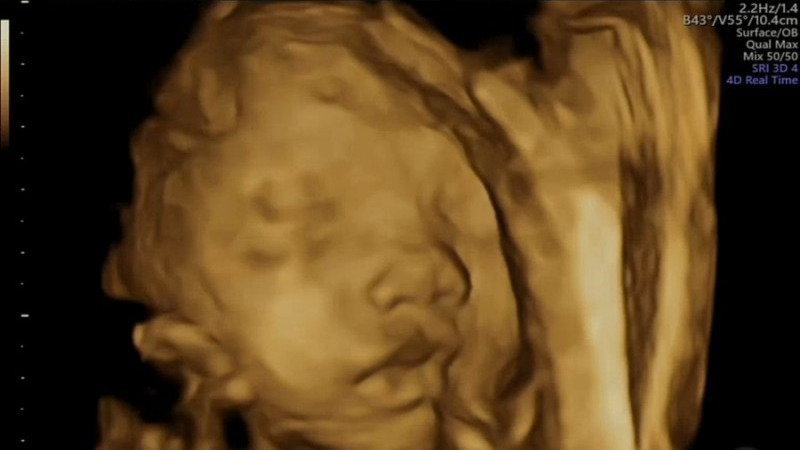

그리고 28주 차에 처음으로 덕순이의 얼굴을 입체 초음파로 볼 수 있었다.

그동안 12주 입체 초음파, 20주 정밀초음파까지 검진을 마쳤지만 덕순이의 얼굴을 자세히 보진 못했다.

12주 때 덕순이는 손가락 마디만 한 6.4cm로 입체 초음파로도 겨우 사람의 형태를 확인할 수 있을 만큼 작았다. 20주 때는 덕순이의 얼굴을 보는 게 아니라 장기들이 정상적으로 자리 잡았는지, 외적 기형은 없는지 검진했다. 아이의 얼굴은 보통 24주 후부터 입체 초음파로 확인하는데 내가 다니는 병원은 28주에 확인할 수 있었다.

28주 차 검진 날은 처음으로 덕순이의 얼굴을 보는 날인지라 무척 떨렸다. 남편도 무리해서 반차를 내고 병원에 같이 와서 함께 덕순이의 얼굴을 보았다.

떨리는 첫 순간, 덕순이는 필사적으로 얼굴을 가리고 있었다. 두 손으로 얼굴을 감추고 있었는데

검진을 봐주시는 선생님이 능숙하게 배를 이리저리 흔들었다. 기침도 해보고, 옆으로도 누워보고, 덕순이 입장에선 평화롭게 있다가 얼굴 좀 보자고 이리저리 괴롭히는 것이 꼭 봉변일 것만 같았다.

아마 덕순이가 끝까지 얼굴을 안 보여줬다면 덕순이를 위해 재시도는 포기했을 것 같다. 하지만 다행히 덕순이는 손을 살짝 내려주었고 선생님이 그 찰나를 놓치지 않고 얼굴을 찍어주었다.

탯줄에 조금 가려져있었지만 두 눈, 코, 입이 모두 보였다. 큰 눈두덩이를 보니 왠지 오빠 눈을 닮았을 것 같단 희망이 보였다. 코는 우리 둘을 닮아 오뚝했다.

신기한 건 입술이었다. 남편이 남자치고는 입이 가로로는 짧고 도톰한데 덕순이가 남편의 입술을 빼닮았었다. 아니, 덕순이가 좀 더 도톰하게 생겼다.

큰 눈에 오뚝한 코, 도톰한 입술까지...

우리 둘 사이에서 생긴 게 믿기지 않을 정도로

너무 예쁘고 귀여웠다. 내 아기라서 예쁜 건지, 객관적으로 예쁜 건지 구분이 안 가지만 확실한 건 내 눈에는 세상에서 제일 예쁜 아기였다. 이 아기가 내 뱃속에 있다는 것도 사실 믿기지 않았다. 임신했다는 사실은 알고 있지만 내 뱃속에 다른 심장이 뛰고 있다는 사실은 늘 신비롭고 놀랍다.